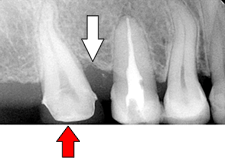

| 赤矢印の方向に咬む力が加わると 白矢印部分の骨が吸収していきます。 |

| 矯正により正しい方向に力を加えられるようになりました。 | ||

| 虫歯が大きくこのままではうまく被せられません。 | 矯正により歯を引っ張りあげます。 | |